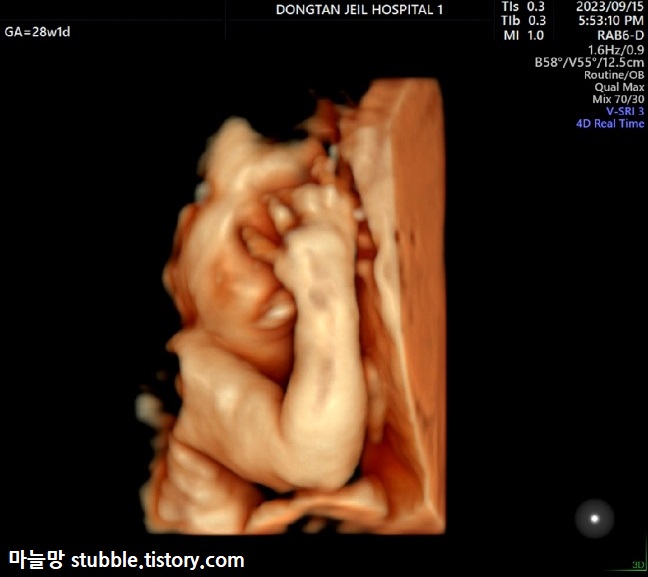

생각보다 아기가 잘 움직인다는 이야기를 듣긴 하였지만 탯줄이 얼굴 위로 지나가고 있었고 아기는 태아 기본자세[?]인 팔을 귀 옆에 두고 절대 내리지 않아서 아주 힘든 초음파를 보게 되었습니다.

그 와중에 얼굴을 가로질러 탯줄이 지나가고 있었는데, 탯줄을 한쪽손으로 잡고 있는 태아의 모습입니다. 탯줄 혈류체크한 것도 보입니다. 입체초음파로 변환했는데도 탯줄은 꽉 잡고 놓지 않았어요.

믿어지지 않겠지만 이게 오늘 제일 잘 나온 입체초음파 사진입니다. 이것마저도 정확하진 않겠지만 그나마 얼굴이 다 나온 사진입니다. 복도를 5분 동안 걸어도 손과 팔이 얼굴로 향해있던 아가. 이제 얼굴 보려면 출생해서 봐야 할 것 같아요.